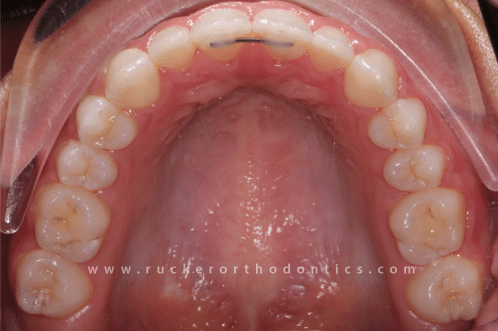

A bonded retainer, also known as a permanent retainer, is a type of metal retainer wire that is glued to the back of your teeth. They are typically placed on the lower teeth from canine to canine, but are also placed behind the upper teeth in certain situations. Although they are not permanently glued to your teeth, you will often them referred to as "permanent retainers." The reason for that is because bonded retainers are not removable by the patient. However, they can always be removed by a dental professional. With a little polishing of the glue that holds the wire in place the bonded retainer can be removed, leaving the tooth enamel in a healthy condition.